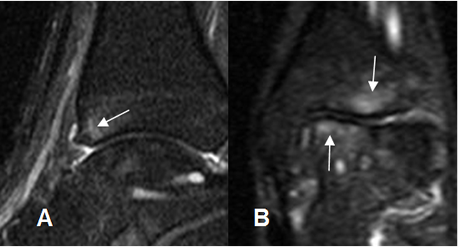

Con la RM se valora el grado de daño cartilaginoso (16). Además se aprecia el edema óseo y los signos de sinovitis en el receso capsular anterior. (15). (Fig 90, 91).

Fig 91. Pinzamiento anterior.

A: RM sagital y B: RM coronal en STIR. Edema óseo en la tibia y el talo, por el microtrauma repetido.